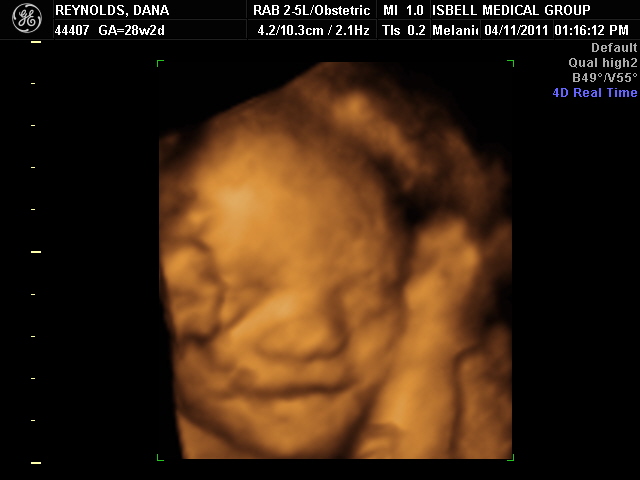

A couple of months ago, I briefly mentioned that Jack will be getting a new cousin- my sister and her husband are having their first child.  They recently found out it’s a girl!  My sister’s due date is July 2nd, which means that her daughter and Jack will be in the same school grade.  Here’s the most recent picture of her: